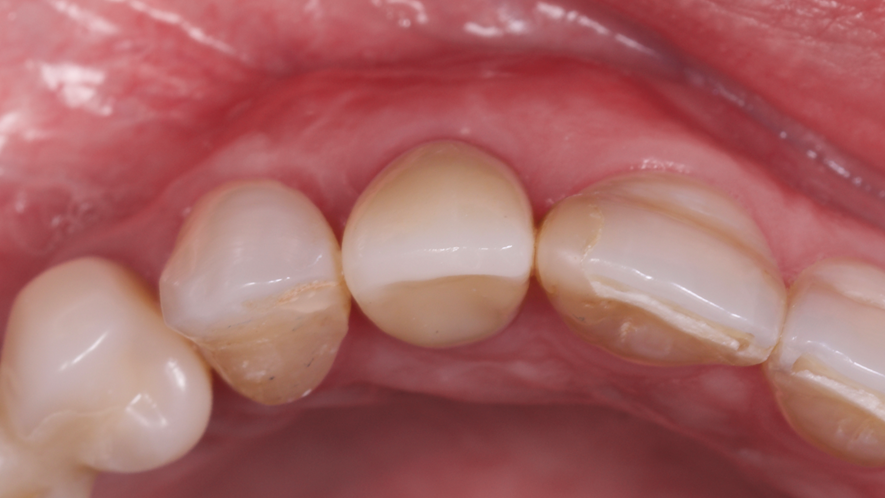

A restauração imediata pode apresentar algumas vantagens, como encurtar o tempo de tratamento, eliminar o uso de PPP ou provisórios ligados a dentes adjacentes, alta aceitação do paciente, eliminação da reabertura do implante e benefícios estéticos, sociais e psicológicos. A preservação do osso e das papilas dos dentes adjacentes ainda é citada como uma vantagem desta técnica5.

Os implantes Cone Morse foram criados com o intuito de minimizar problemas recorrentes na prática clínica odontológica, buscando maior segurança e longevidade das próteses fixas sobre os implantes e mostrando grandes resultados na estética6. O conceito Cone Morse apresenta vantagens protéticas significativas em comparação aos implantes hexágonos, principalmente em elementos unitários anteriores, tendo em vista que a longevidade da estética gengival é de suma importância, demonstrando qualidades clínicas, biológicas e biomecânicas superiores7.

Este trabalho tem como objetivo relatar um caso clínico de exodontia minimamente invasiva de um incisivo lateral superior com fratura radicular, realizando implante imediato em alvéolo pós-extração, enxerto de tecido conjuntivo subepitelial e osso bovino liofilizado para preenchimento de GAP, prontamente à instalação de pilar reto e provisório imediato.